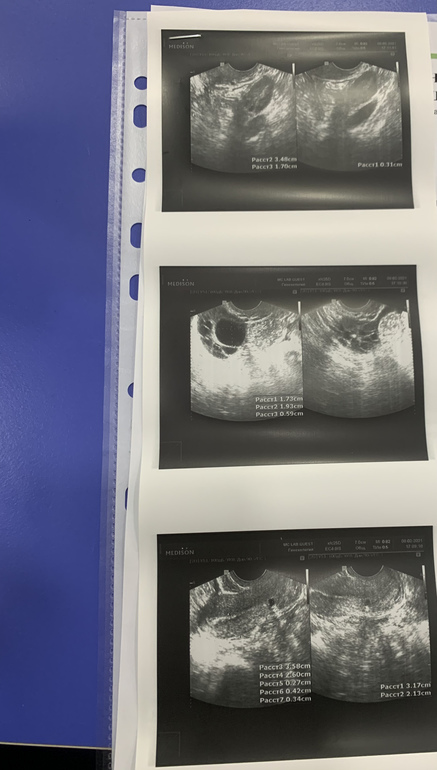

Очень странные размеры указаны,и фолликулы как кисты(0.31см)это 30 мм же получается?это уже как киста фолликулярная.сходите к врачу пусть посмотрят.Я просто УЗИ и фолликулометрию делаю каждый цикл у меня уже этих бумажек тонна...как то странно у вас.

Узи делала , ничего подобного не было(но аппарат был старее) тут говорят что эндометрий очень тонкий и цикл в этом месяце без овуляции будет .